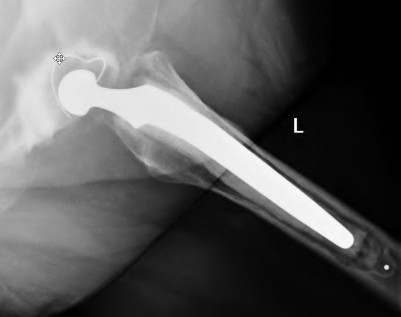

A 75-year-old female sustains a fall 5 years after a cementless THA. Radiographs show a periprosthetic femur fracture occurring around the stem tip. Intraoperative assessment reveals the stem remains firmly fixed in the metaphysis, and the proximal bone stock is adequate. According to the Vancouver classification, what is the fracture type and the standard recommended treatment?